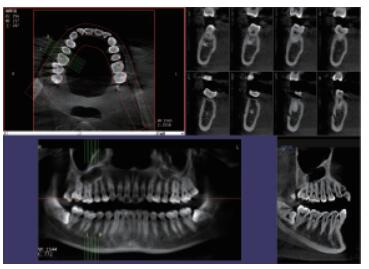

你知道口腔CBCT是什么意思嗎?口腔CBCT是一類特殊的CT,其工作原理是通過X線發(fā)生器以較低的射線量發(fā)射錐形X束,圍繞投照體做環(huán)形數(shù)字式投照,將圍繞投照體多次產(chǎn)生的二維投射影像通過圖像重建算法獲得三維圖像。成像效果更好,有助于醫(yī)生的診斷,對(duì)于種植、綜合診斷、正畸等牙科診斷均有較大幫助。

在口腔影像等細(xì)分領(lǐng)域,口腔CBCT的成像質(zhì)量?jī)?yōu)于CT和普放。CBCT的X線利用率更高,且生成的圖像具備很高的各項(xiàng)同性空間分辨率。CBCT技術(shù)優(yōu)勢(shì)如下:

三維重建任意斷層

專有三維重建算法,可提供任意位置高清斷層影像。

高清口腔全景影像

通過三維容積影像,提取高清口腔全景影像。

多平面組合重建

可同時(shí)觀察軸向面、冠狀面和矢狀面圖像,方便臨床診斷。